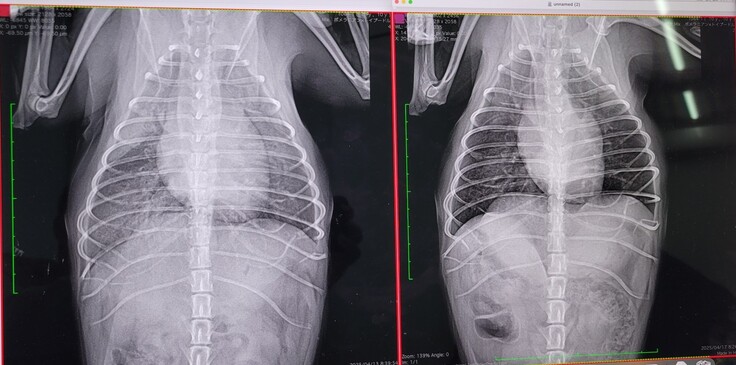

病院では僧帽弁閉鎖不全症のステージC・三尖弁閉鎖不全症・不整脈という重度な状態と診断され、その後しばらく自宅で一日2回の薬で様子を見ていましたが、少しずつ咳が出始め、6月2日に再度失神し、肺水腫も再発しており2度目の入院となりました。(6月5日退院)

左が6月2日で、右が6月5日